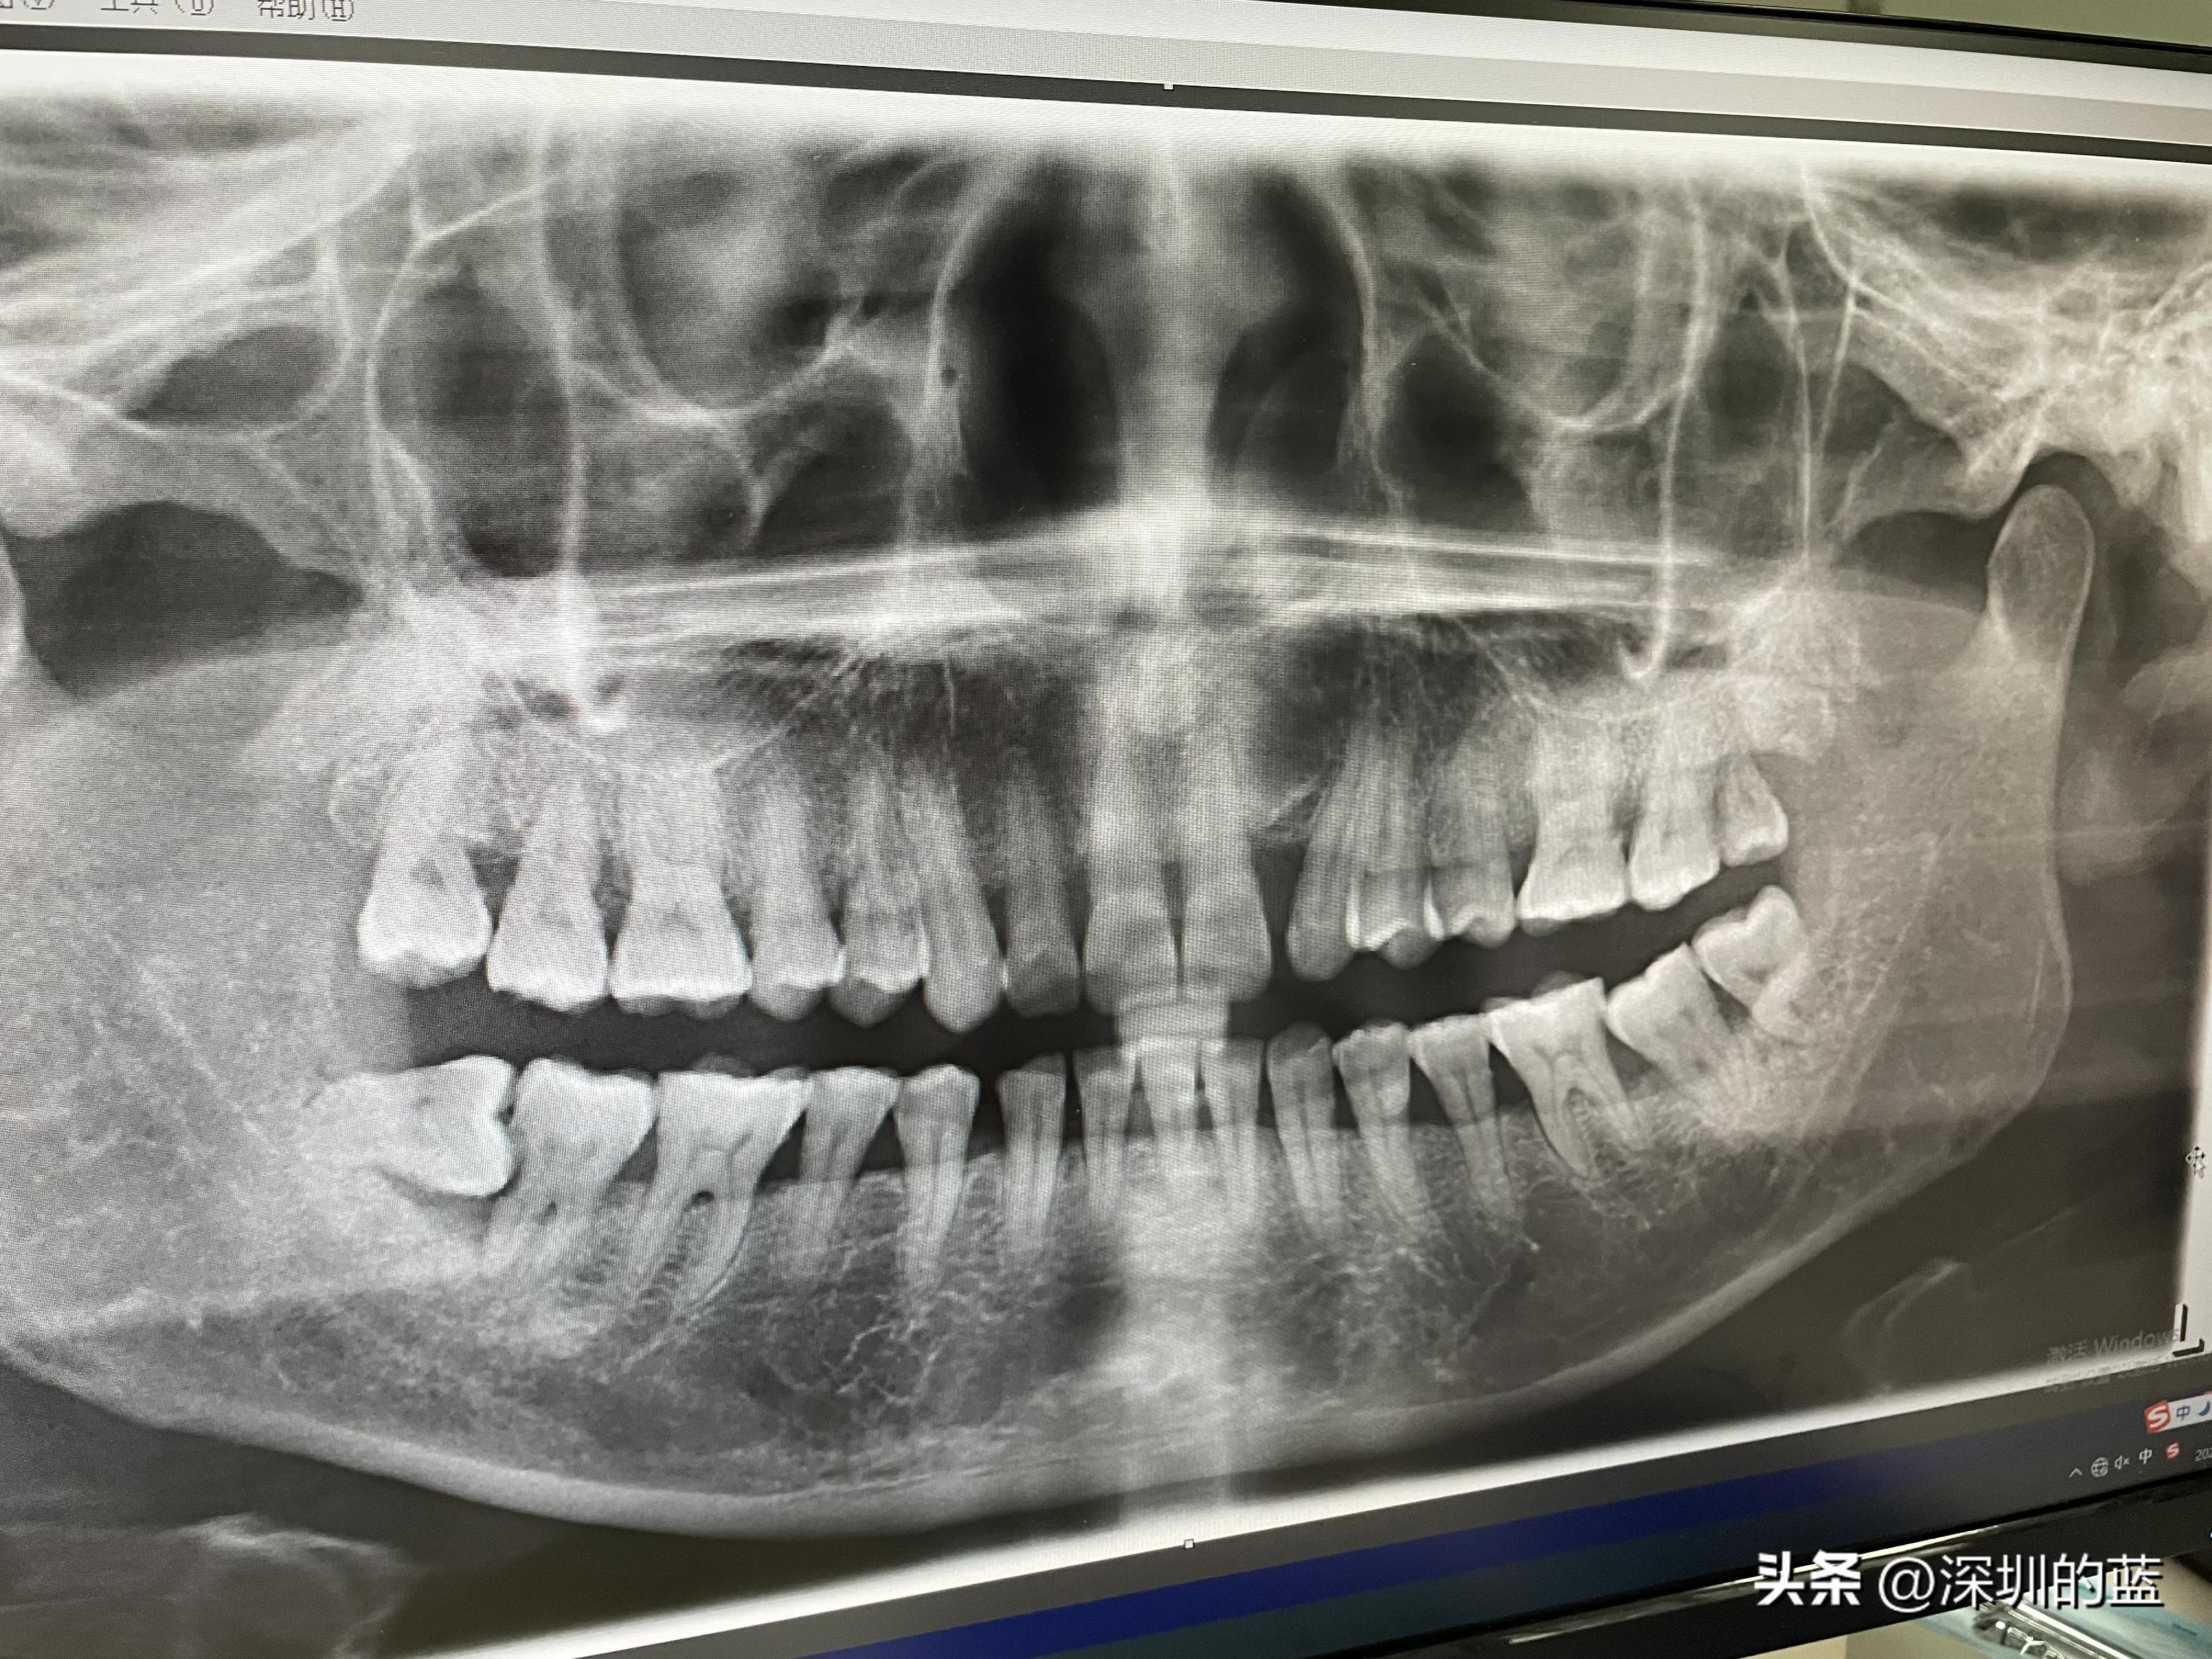

于是,我决定去市医院看牙医,拍了牙齿的全景图,发现有四颗智齿,而且有一颗还是横生智齿,它把它前面邻牙一边的牙脚给插坏了,医生说没有办法修补。所以,第一次拔牙,我不得不把阻生智齿和它旁边的邻牙也一起拔了,打算以后种回一颗牙齿。